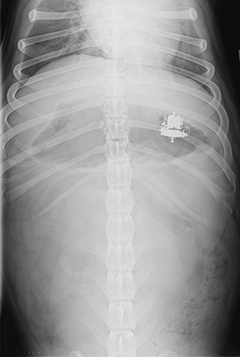

Your primary care veterinarian will likely recommend initial blood work that includes a complete blood count (CBC), serum chemistry, and a urinalysis. These combined, will help to rule out other causes for your pet’s symptoms. Abdominal, and occasionally thoracic, radiographs (X-Rays) are regularly performed (Figures 2 and 3). Positive contrast radiographs (using barium to highlight the inside of the stomach and intestines) may be performed when routine radiographs fail to show the cause for the clinical signs. Abdominal ultrasound can be very helpful in identifying gastrointestinal foreign bodies. In some cases, advanced imaging, such as a CT scan, may be needed.